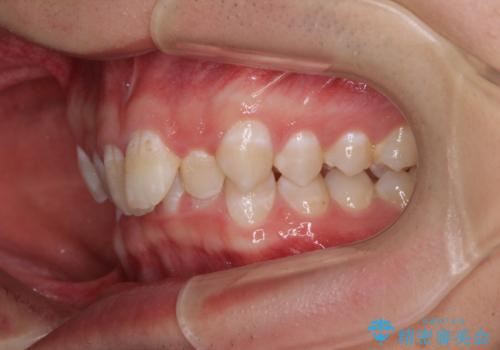

下顎前歯が全て隠れてしまうほどの深い咬合で、左右の奥歯は1歯対1歯で咬み合う状態でした。

前方に移動している上顎臼歯を補助装置にて遠心移動させることで1歯対2歯の臼歯咬合を目指し、同時に深い咬合を改善していくこととしました。